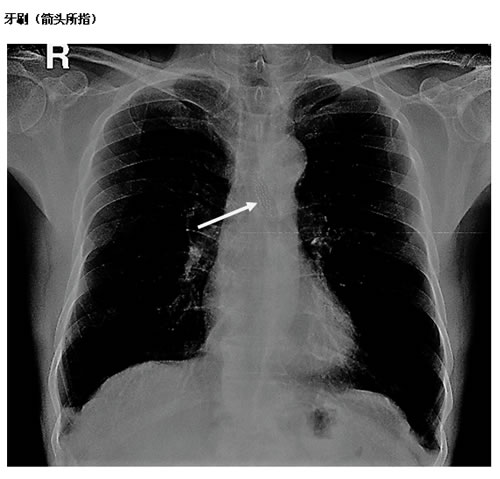

上周末就有一位大叔晨起刷牙太认真,过分用力,一不留神把牙刷刷断了,没等他反应过来又一不小心咽进了肚子里,呕又呕不出来,胸口一阵发闷。大叔赶紧去医院就诊,首诊医院把他转送到市二医院。X光片检查看到一只牙刷头样物体在食管中段,正卡在心脏上方,马上转诊到消化内科。消化内科大夫立即安排胃镜检查,胃镜下见到一只牙刷头正嵌顿在食管狭窄段,用器械完整取出,一量,整整6厘米长。幸好诊治及时,食管粘膜无明显损伤,取出牙刷后大叔胸口不适感完全消散,回家重新刷牙去了。